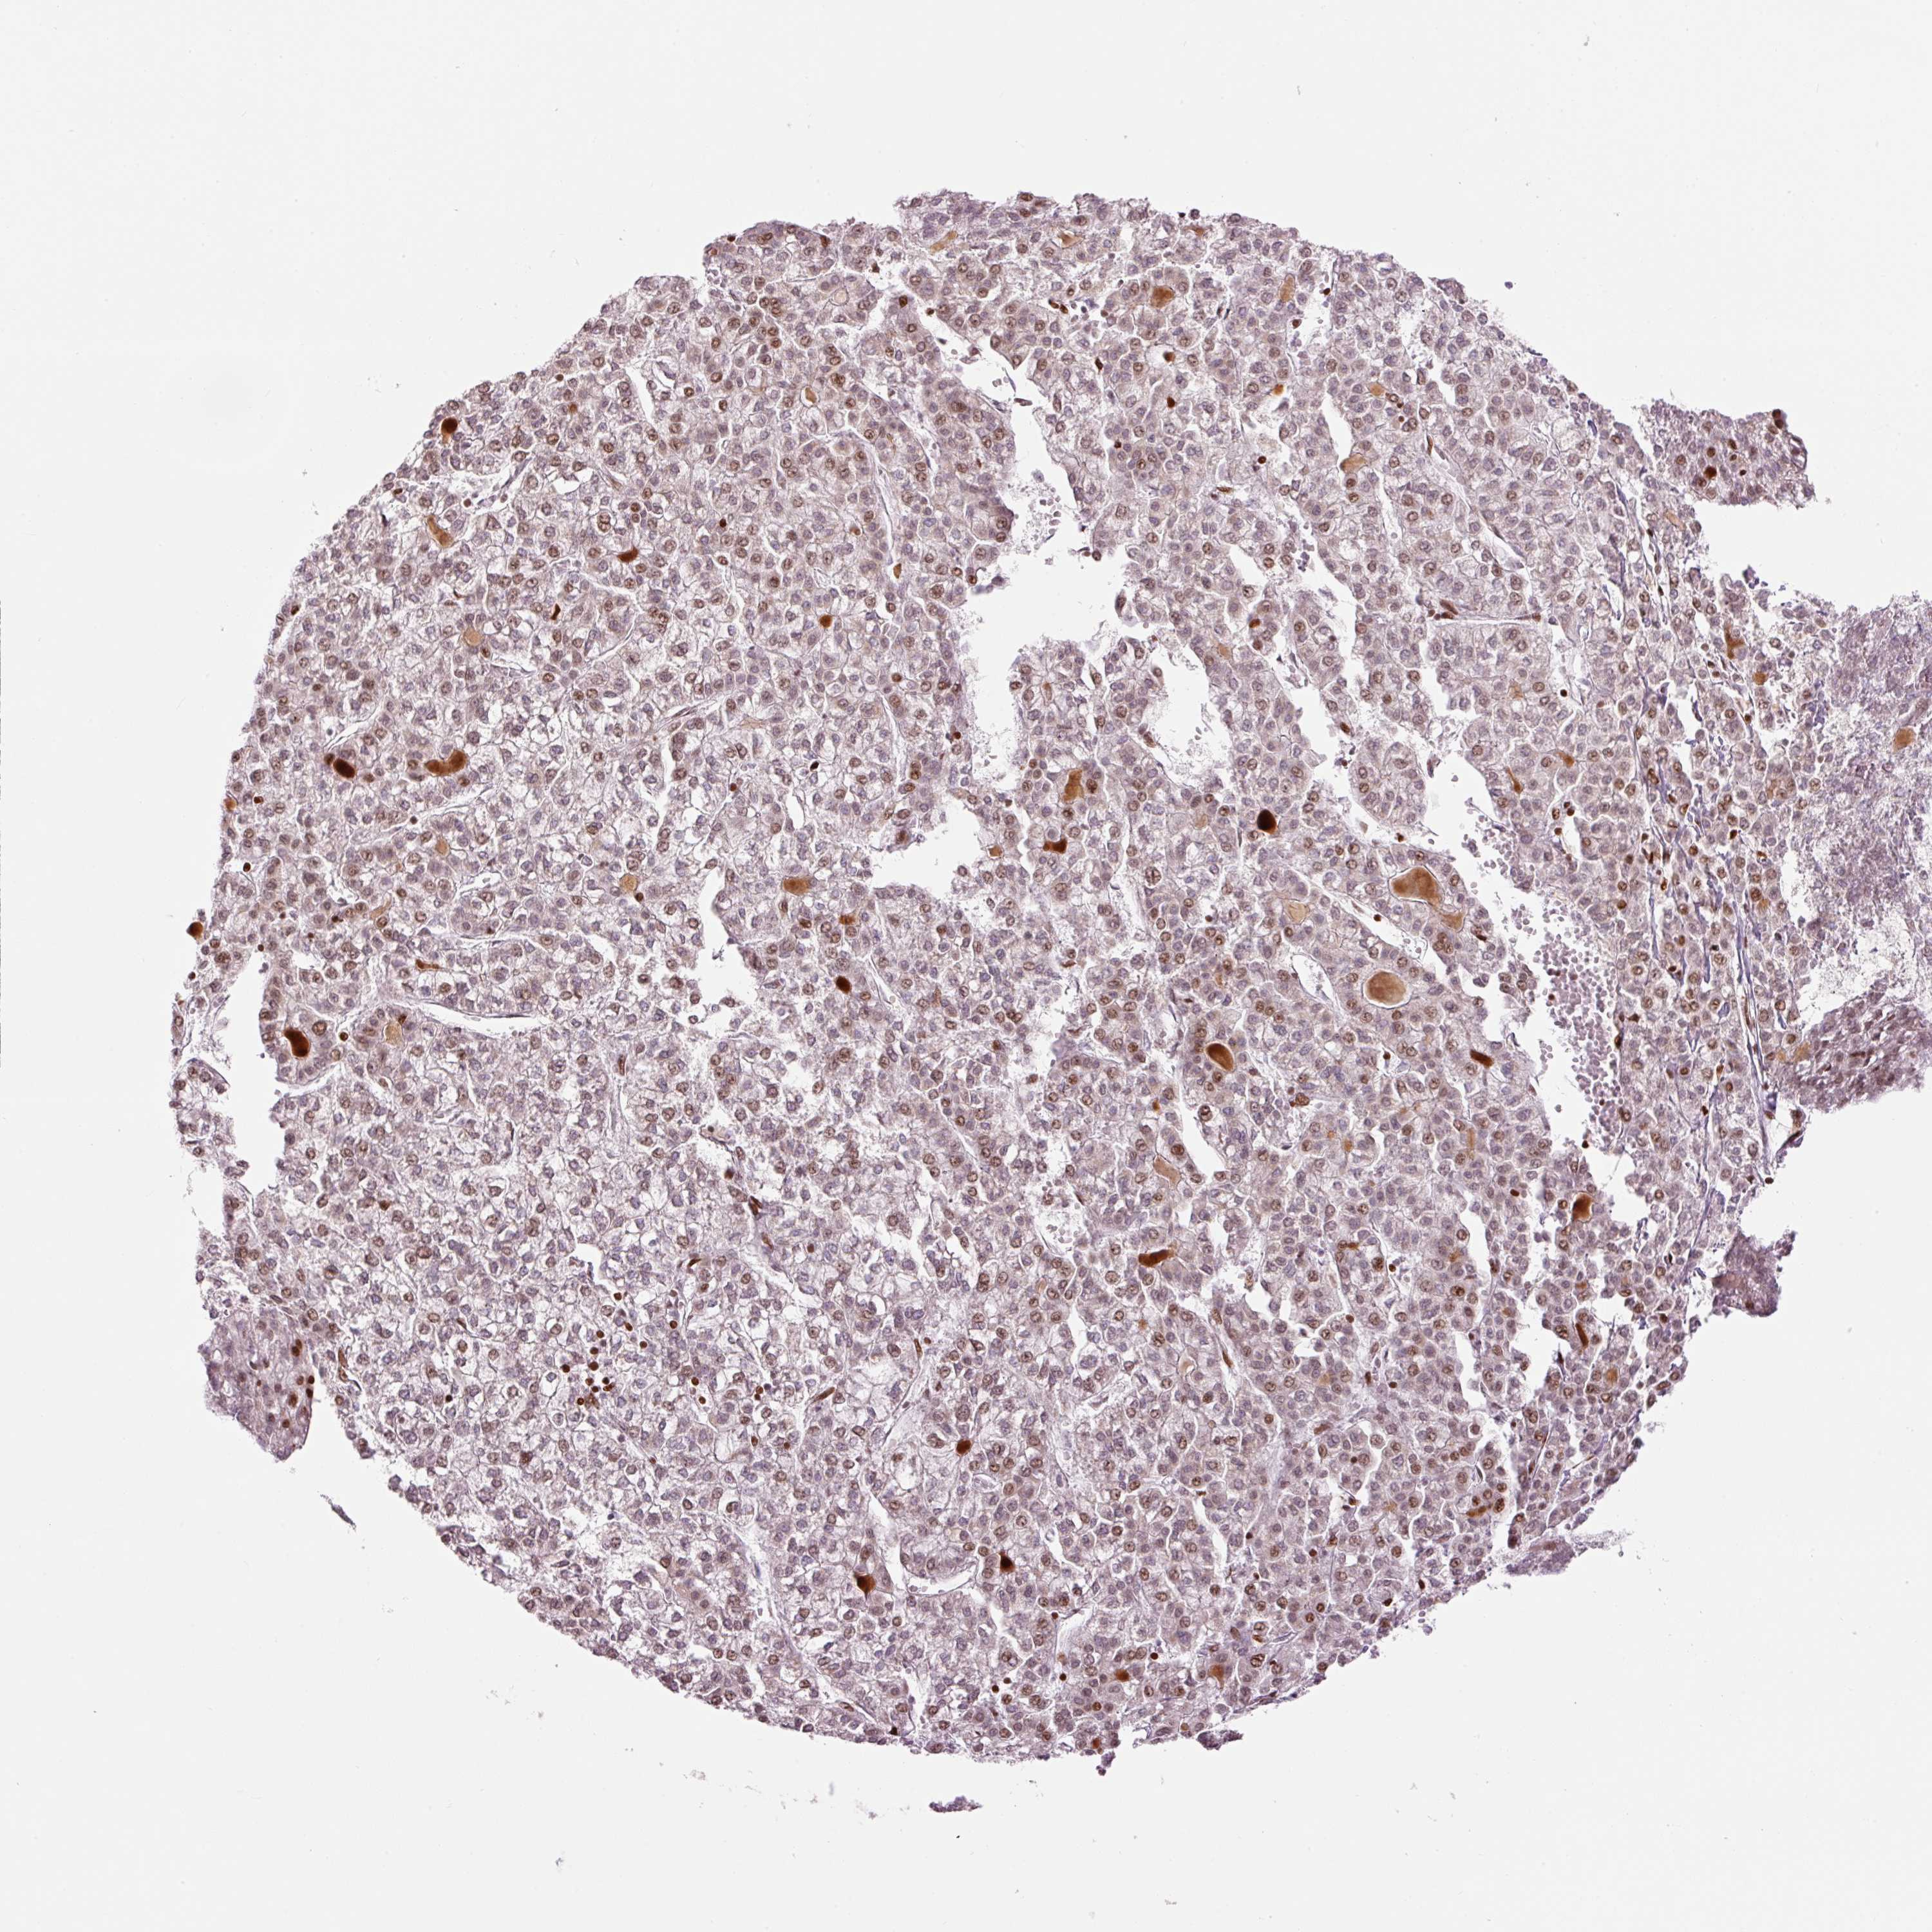

LIVER CANCER - Protein expressioni

A mouse-over function shows sample information and annotation data. Click on an image to view it in a full screen mode. Samples can be filtered based on level of antibody staining by selecting one or several of the following categories: high, medium, low and not detected. The assay and annotation is described here.

Note that samples used for immunohistochemistry by the Human Protein Atlas do not correspond to samples in the TCGA dataset.

Antibody stainingi

Antibody staining in the annotated cell types in the current human tissue is reported as not detected, low, medium, or high, based on conventional immunohistochemistry profiling in selected tissues. This score is based on the combination of the staining intensity and fraction of stained cells.

Each image is clickable and will lead to virtual microscopy that enables deeper exploration of all samples and also displays staining intensity scores, fraction scores and subcellular localization as well as patient and tissue information for each sample.

Antibody HPA053816

Staining

High

Medium

Low

Not detected

Intensity

Strong

Moderate

Weak

Negative

Quantity

>75%

75%-25%

<25%

None

Location

Nuclear

Cytoplasmic/membranous

Cytoplasmic/membranous,nuclear

Carcinoma, Hepatocellular, NOS

Cholangiocarcinoma